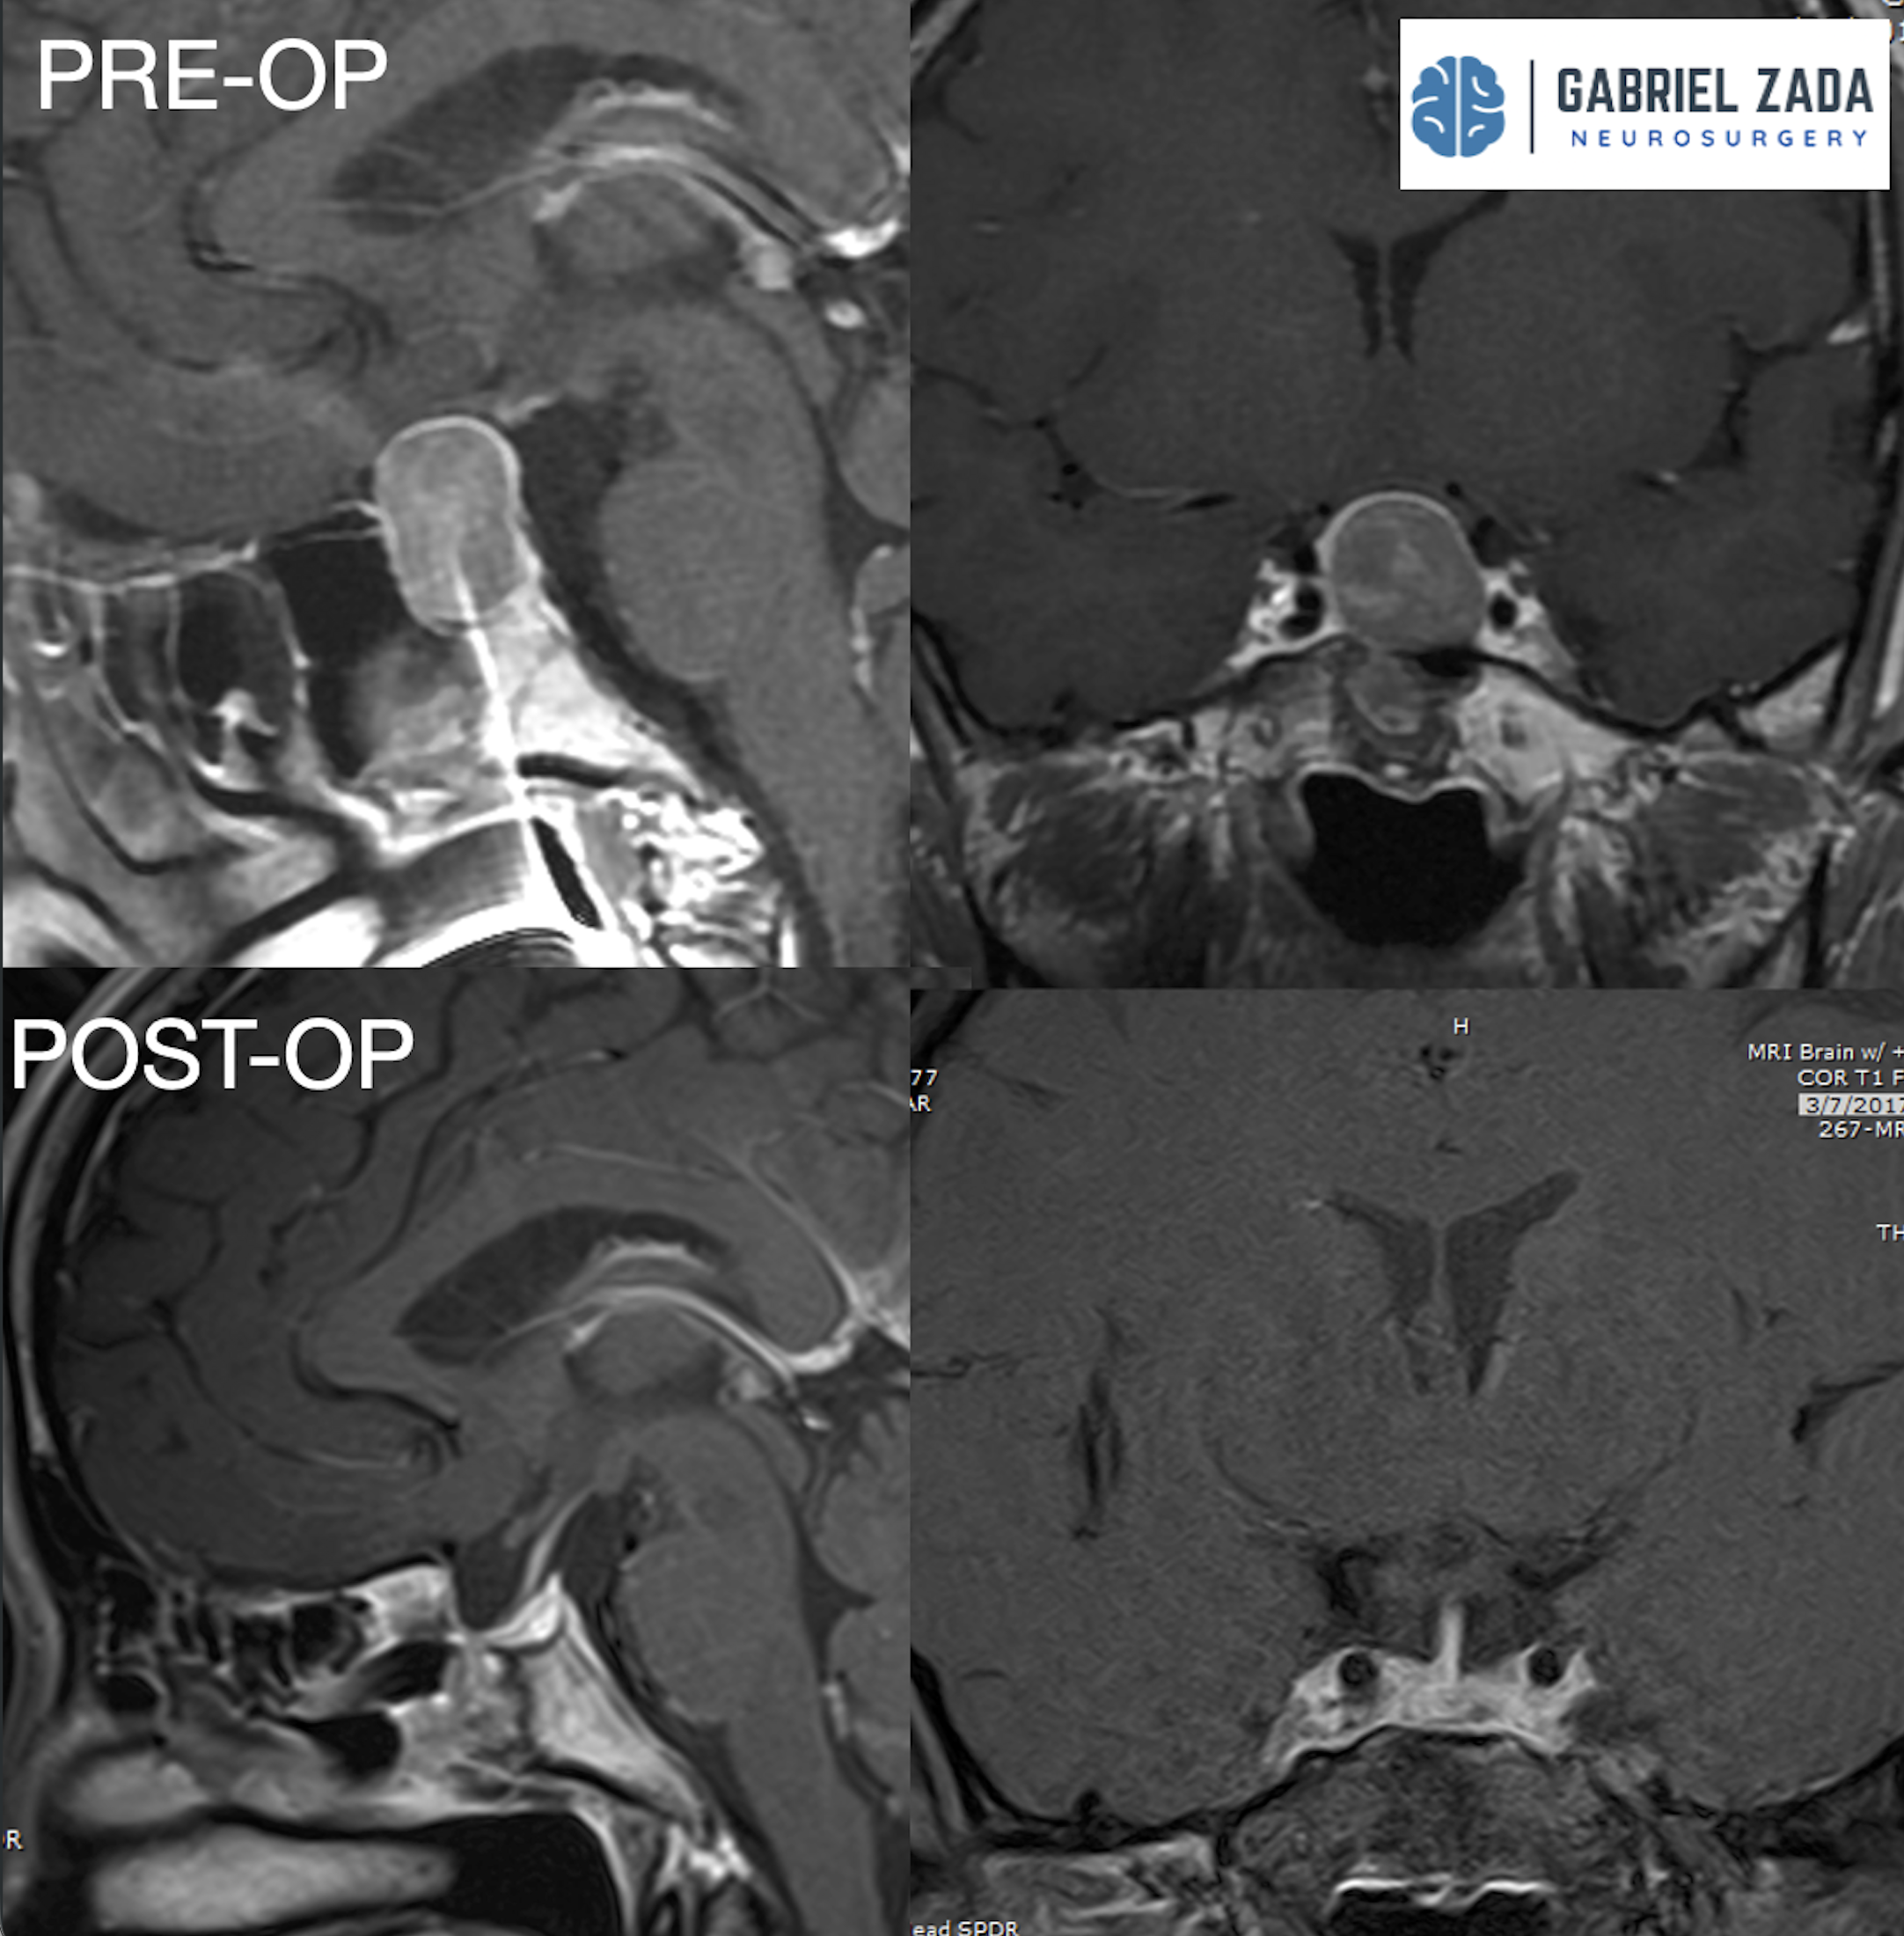

Explore this comprehensive gallery featuring pre‑ and post‑operative imaging of patients with skull‑base tumors treated by Gabriel Zada, MD, MS, FAANS, FACS. These cases highlight Dr. Zada’s expertise in advanced neurosurgical techniques and outcomes.

*Representative cases shown for educational purposes. All images de-identified. Individual results vary.